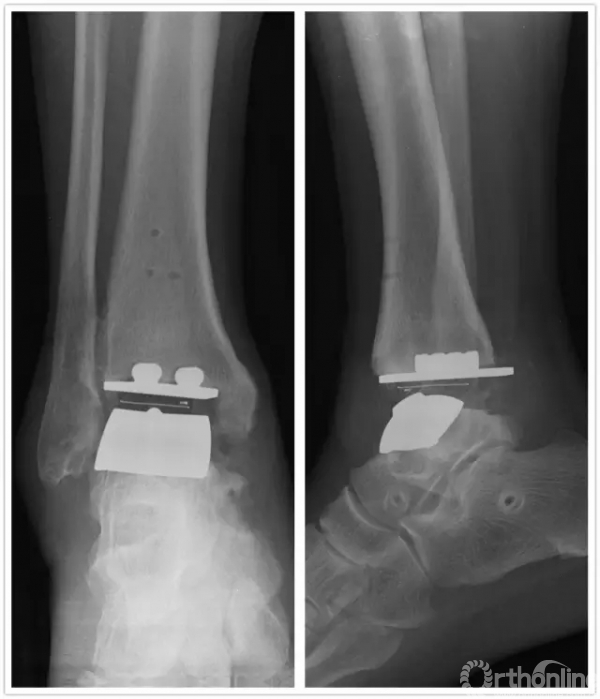

方老伯,今年67岁,2006年7月他因左侧踝关节严重骨关节炎到上海瑞金医院就诊,当时刘津浩副主任考虑其踝关节和距下关节都已经出现严重的骨关节炎,无法保留关节,于是对其进行了胫距跟双关节融合手术。手术后方老伯恢复良好,如期达到骨性融合。2年后,方老伯右侧踝关节开始出现肿胀疼痛,日夜反复发作,直到2010年2月,他无法忍受,再来医院就诊,拍片后发现他右侧踝关节也出现明显骨关节炎。此时正值瑞金医院足踝外科全面发展时期,足踝外科的新理念、新技术已经引入瑞金医院,当时学科带头人徐向阳主任认为该患者左侧踝关节已经行融合手术,右侧不适宜再行融合手术。于是徐主任主刀、刘津浩副主任和朱渊医师担任助手,顺利为方老伯进行了踝关节STAR假体置换术,手术后保持随访康复良好,又恢复了往常的劳作。

直到1年前,方老伯感觉右侧踝关节又开始出现肿胀疼痛,劳作后加重,最近越来越重。2016年7月再来徐主任门诊复查,徐主任考虑踝关节假体出现了松动,距骨有了塌陷,关节力线有所偏移。鉴于目前瑞金医院足踝外科已经开展踝关节INBONE假体置换术,积累了一定的经验,于是徐主任向患者及家属解释病情,建议再行踝关节翻修术。